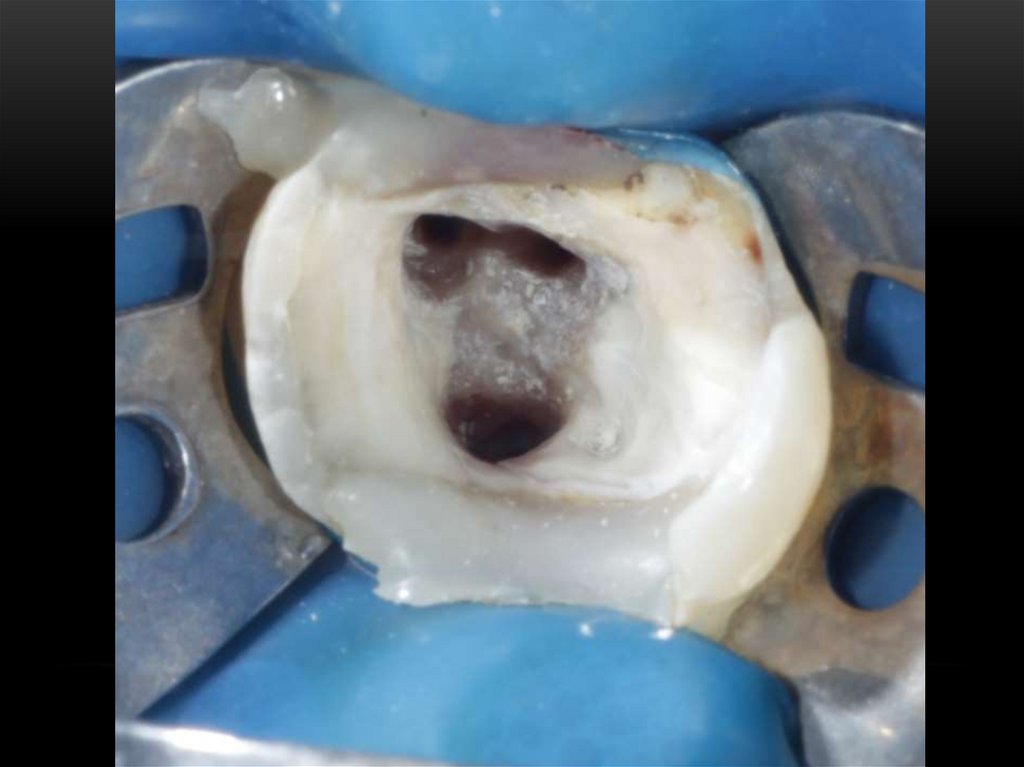

Механическая обработка корневых каналов. Этапы эндодонтического лечения

Принципы препарирования корневых каналов. Алгоритмы эндодонтического лечения

Эндодонтическое лечение зубов. Инструментальная обработка корневых каналов. Лекция 3-4

Ирригации корневых каналов

Механическая обработка корневых каналов

Лечение корневых каналов